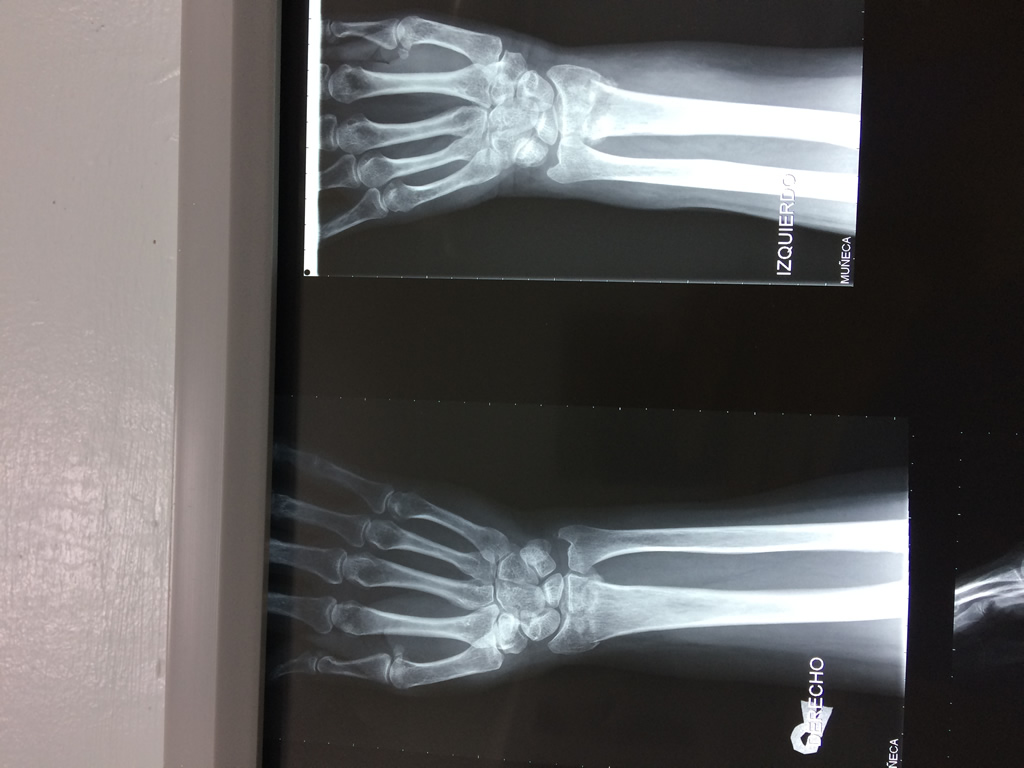

Cirugías de Calcaneo - Cirugías de Muñecas y Manos

Los procedimientos más comunes en cirugía de la mano son aquellos destinados a reparar traumatismos, incluyendo lesiones de tendones, nervios, vasos sanguíneos, y articulaciones; huesos fracturados; y quemaduras, cortes, y otros daños de la piel.